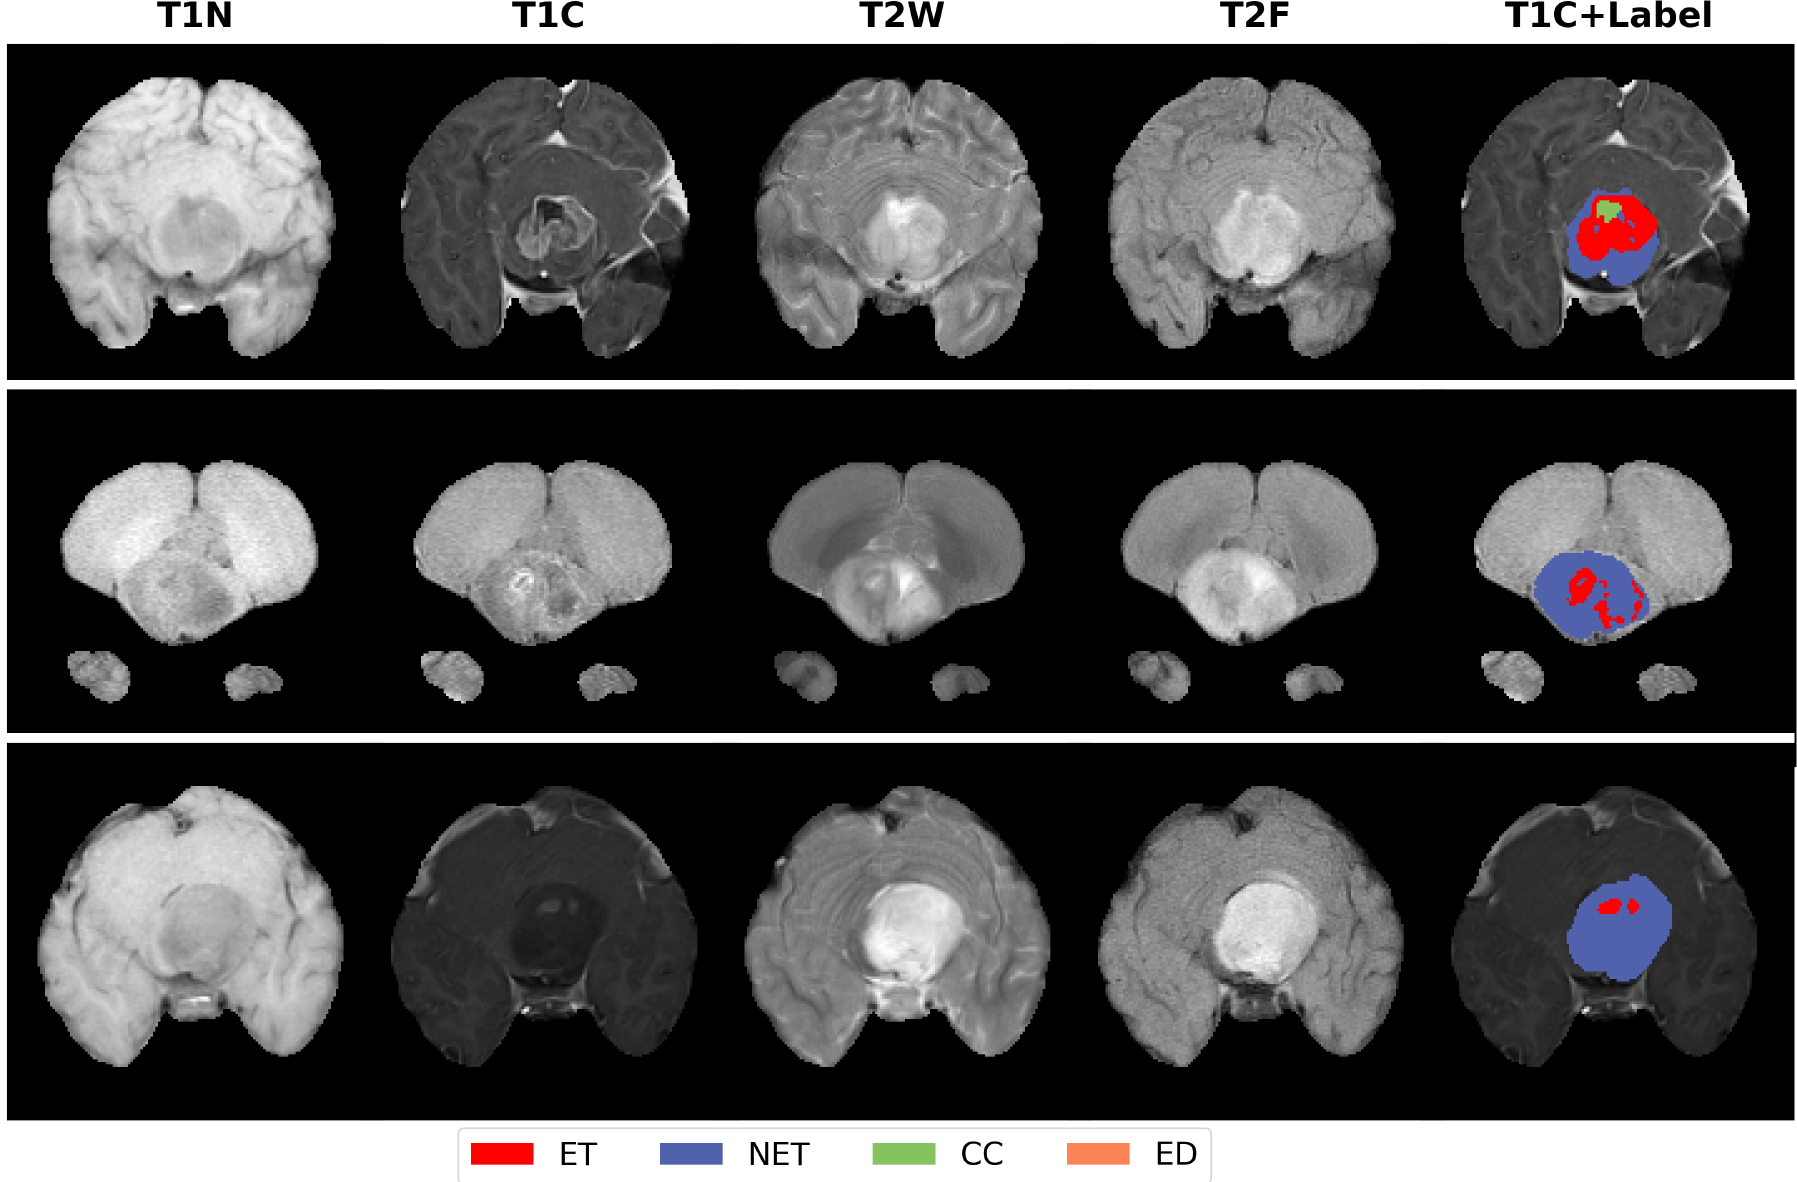

Refer to caption

Figure 3: Quantitative results of the final model on the validation set. The three selected examples correspond to BraTS-PED-00310-000, BraTS-PED-00315-000, and BraTS-PED-00318-000, respectively.

Fig. 3 presents the qualitative segmentation results of the final ensemble model on validation data. The validation set underwent the same skull stripping and frequency domain decomposition pre-processing.